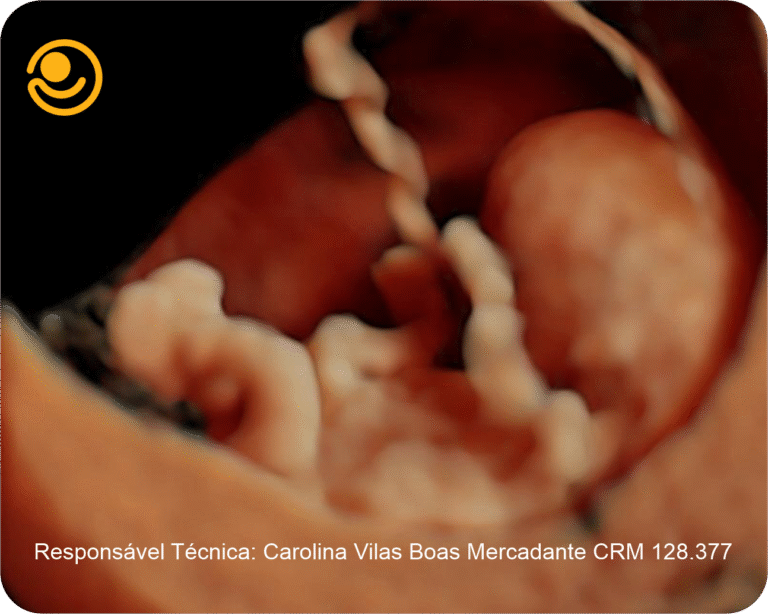

3D / 4D Live – Maior realismo nas imagens e mais precisão nos diagnósticos.

Imagens 3D / 4D

✓ Ultrassonografia 3D/ 4D com imagem em HD